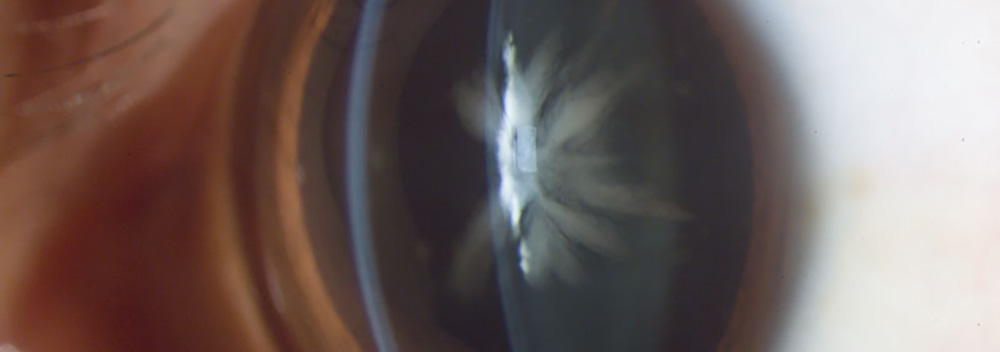

Catarata Congénita, Fotografía, Instituto Barraquer de América